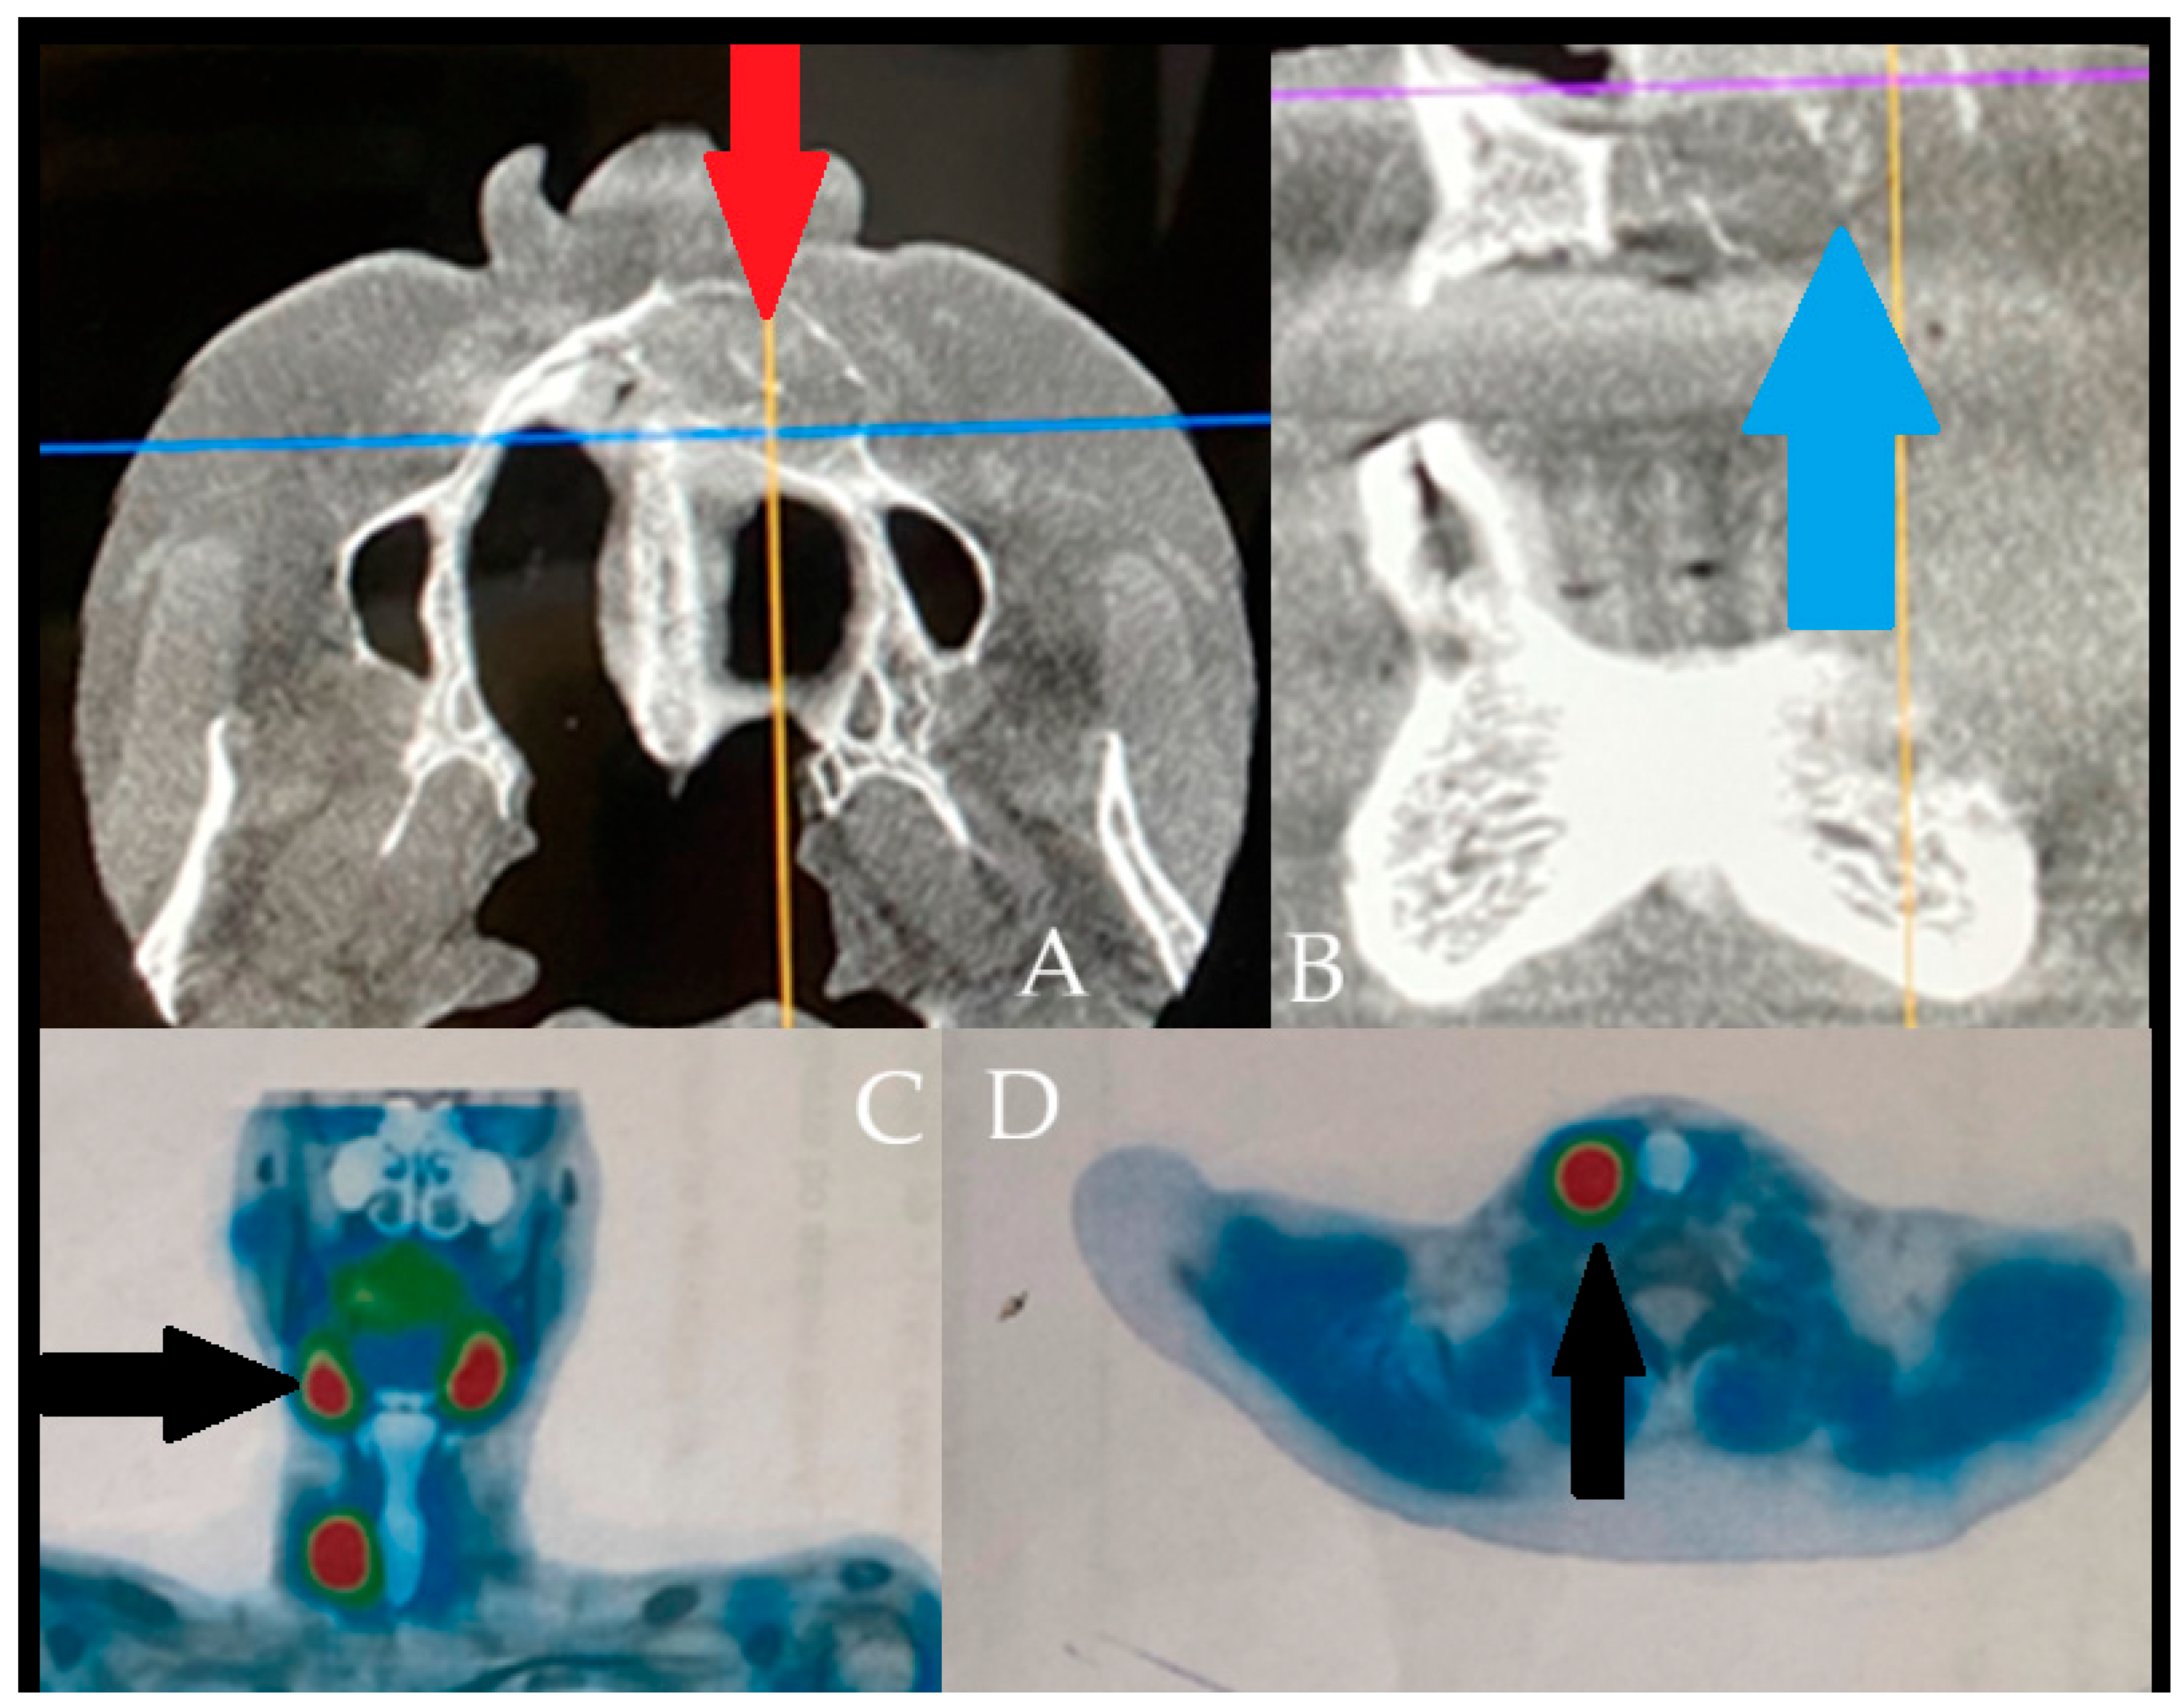

The following figure is a comparable case image to the presented case; however, the BT lesions found were not that advanced locally and were misdiagnosed as other minor jaw lesions. However, the performance of SPECT-MiBi improved greatly on the final diagnosis. The occurrence of BT is a very troublesome disease in identification in some atypical cases, especially in small lesions, without significant aggressive bone loss, extracortical spread, and when they have a similar appearance to a normal jaw cyst [8,9]. The differential diagnostics might be difficult, when some bone lesions in jaw bones can mimic a vast scope of other tumors and lesions of both benign and malignant origins ((A,B) with blue-orange and purple-orange orientation lines). Sometimes, regardless of a full blood-work and evaluation of calcium-phosphatase markers, very good radiology, the full scope of the disease might often be camouflaged by other general patient co-morbidities. In cases of any doubts, a special scintigraphy of the parathyroid glands (SPECT-MiBi) (Black arrows, (C,D)) is very important, along with a biopsy to fully confirm this disease [2,4,8]. The scope of BT in PHP/SHP might have many levels of bone changes, blood serum markers exhibition, and, therefore, histopathology. Acquiring more valuable material for accurate histopathology is quite important. The following factors may be associated with various bone changes, the spectrum of lesions, and osteolytic processes detected within a single biopsy specimen. BT can manifest in various ways and with different possible radiological appearances, which are greatly dependent on the scope, intensity, and duration of PHP/SHP [4,5,6,7]. The scope of the surgical approach towards the parathyroid glands and thyroids, if necessary, should be discussed among endocrinologists and general surgeons after a careful individual examination of each case. Collectively, these reports highlight that BT of the jaws is diagnostically challenging due to their overlap with odontogenic and malignant lesions. Accurate diagnosis requires correlation of imaging with biochemical and histopathological findings, and surgical excision may be necessary when systemic therapy proves insufficient.